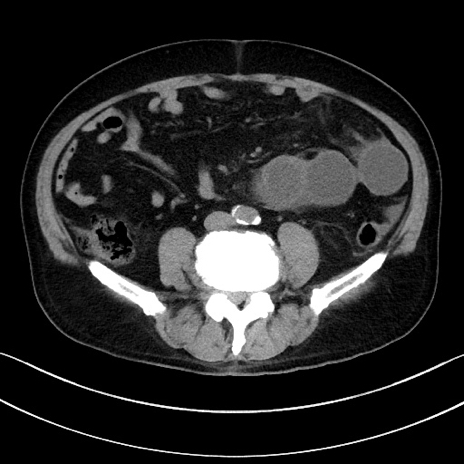

症例15(横断像)

【症例】70歳代男性

【主訴】腹痛

【現病歴】今朝から腹痛あり。全体的に痛い。特に左上の方。排ガスが今日はない。冷や汗が出る。

【既往歴】直腸癌術後

【身体所見】左側腹部〜上腹部に圧痛あり。腹膜刺激症状明らかなではない。軽度反跳痛。左下腹部に術後瘢痕あり。

【データ】WBC 7700、CRP 0.02